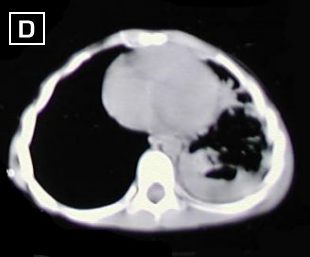

Cortes tomograficos A - B - C - D : Desde carina hacia base del tórax, dezplazamiento de la carina a la derecha, severo engrosamiento pleural izquierdo, con tabicamiento, disminucion del volumen del hemitorax izquierdo, además reporta areas de atelectasia pulmonar en lóbulo inferior izquierdo.